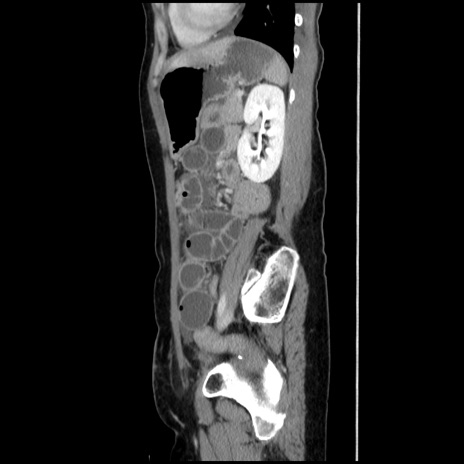

横断像

【症例】40歳代 女性

【主訴】上腹部痛、嘔気・嘔吐

【現病歴】約9時間前頃から急に上腹部痛、嘔気、嘔吐が出現。改善しないため救急要請。

【既往歴】子宮頚癌(広汎子宮全摘術、放射線療法)、腸閉塞

【身体所見】腹部:平坦、軟、腸雑音亢進、上腹部を中心に腹部全体に圧痛あり。

【データ】WBC 8400、CRP 0.03